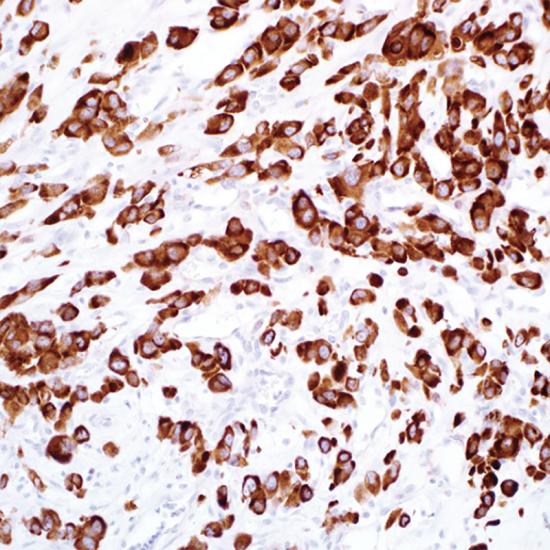

IMP3

IMP3抗體試劑(免疫組織化學) 閩廈械備20180234號

• 陽性部位:

細胞漿

• 陽性對照:

胰腺癌

IMP3是一種致癌胎兒蛋白,屬于胰島素樣生長因子ll mRNA結(jié)合蛋白家族成員。在正常成人組織中,IMP3低表達或不表達,但在惡性腫瘤中,如在胃癌、結(jié)腸癌、胰腺癌、肺癌、腎細胞癌和肝癌中存在過表達。